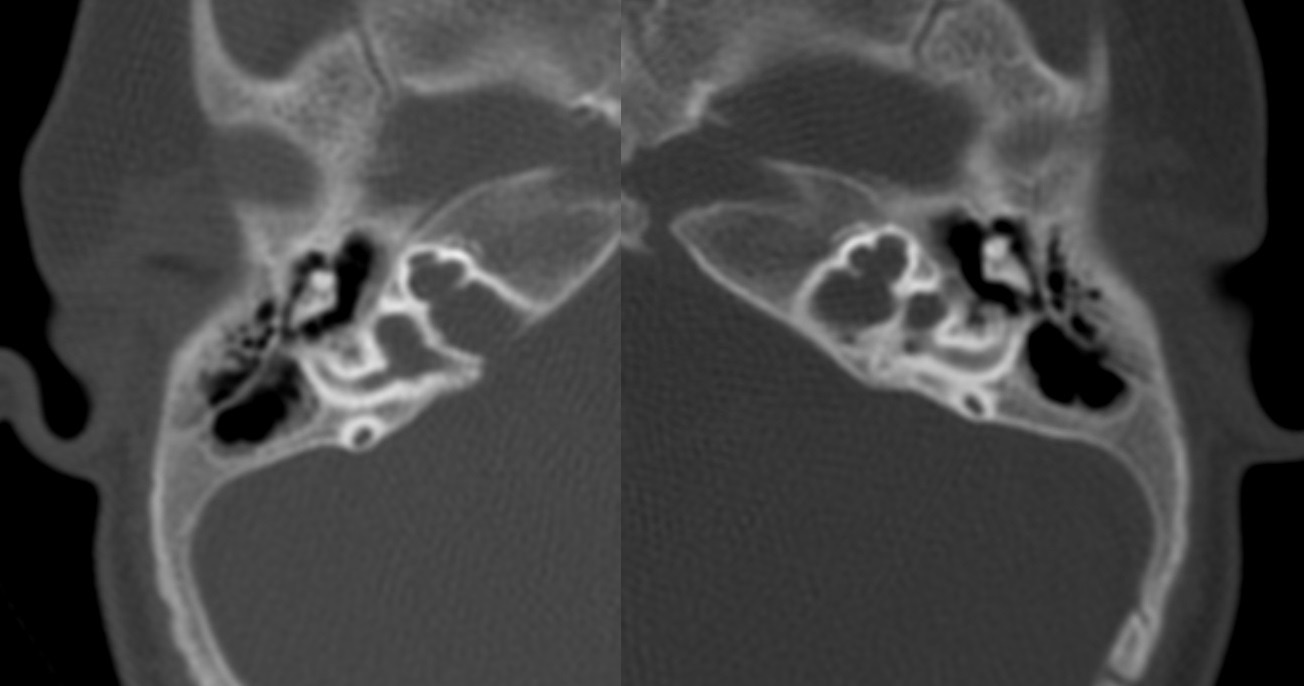

Evaluación de Imagen (TC)

Los hallazgos radiológicos, mediante TC de oídos a cuatro pacientes varones y una madre oyente, portadora obligada, se analizaron y clasificaron según Sennanoğlu et al. [8,9]. En ese sentido, son consistentes con PI-III en tres de ellos: IV-1, IV -2 y IV- 4. El paciente IV-3 mostró PI-I; la madre portadora obligada no mostró alteración alguna (Ver Tabla 3). En los cuatro pacientes estudiados de esta familia observamos dos tipos de MOI, PI-I y PI-III, incluso entre los hermanos IV-2 y IV-3, que presentaron diferente tipo de PI, lo que evidencia expresividad variable. La malformación PI-III es de las MOI menos frecuente y se encuentra presente en este estudio familiar como predominante.

| IV-1 | Ausencia de modiolo con presencia bilateral de septo interescalar | Discretamente amplio | Dilatación parcial en su segmento lateral | PI-III | Imagen 7 |

| IV-2 | De tipo quístico con ausencia bilateral de modiolo | Dilatado con hipoplasia de CSL izquierdo | Aparente estenosis de la entrada del nervio coclear al miodolo | PI-III | Imagen 8 |

| IV-3 | Ausencia de modiolo con presencia bilateral de septo interescalar | Dilatación en su segmento lateral | PI-I | Imagen 9 | |

| IV-4 | Ausencia de modiolo con presencia de septo interescalar bilateral | Discretamente amplio | Dilatación en su segmento lateral | PI-III | Imagen 10 |

| III-2 | Normal | Normal | Normal |

Abreviaturas: MOI: Malformación de oído interno; PI-III: partición incompleta de cóclea Tipo III; CSL: canal semicircular lateral; PI-I: partición incompleta de cóclea Tipo I.

| IV-1 | HNS severa derecha con curva de perfil irregular. HNS profunda izquierda con restos auditivos, congénita | PI-III | 3 y 7 |

| IV-4 | HNS profunda bilateral con curva de perfil irregular derecha y curva plana izquierda, congénita | PI-III | 5 y 10 |